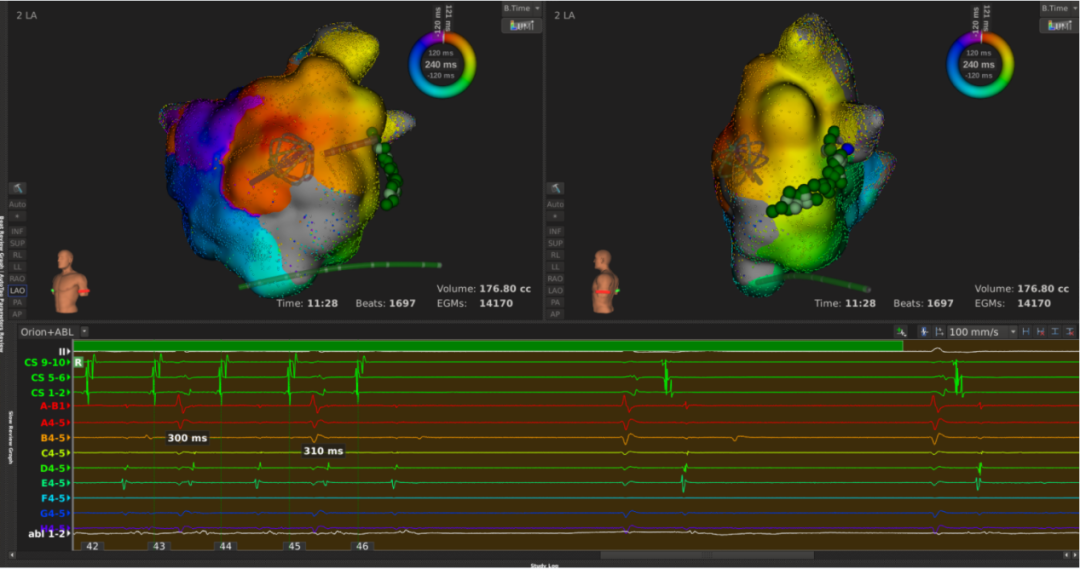

患者上台常规消毒铺巾,心电图显示心房扑动,周长为240ms,穿刺后,先行右房标测,标测结果显示最早激动点由冠状窦口传出,右房整体激动时间占心动过速周长约1/2。遂穿刺房间隔至左房,左房标测结果可见该心动过速绕二尖瓣进行折返,切换电压基质图可见顶部线已断,前壁线区域部分恢复,疤痕部分参与传导。遂先行消融前壁线,以40w 43℃功率模式放电,放电过程中平均单点阻抗下降约25Ω。至前壁线消融结束,心动过速周长延长至260ms. 再行消融二尖瓣峡部线,自瓣环拉至左下肺静脉过程中,DIRECTSENSE™局部阻抗监测技术显示单点阻抗下降约12Ω,心动过速周长逐渐延长至300ms,消融左下肺静脉口蓝点处,心动过速终止。巩固消融后,起博验证,二尖瓣峡线隔离成功。反复burst刺激诱发未见心动过速,本次手术结束。整台手术仅历时90分钟,病人术后感觉良好。

李岳春主任指出该病人病情复杂,能又快又好完成手术,Rhythmia三维标测系统和DIRECTSENSE™(局部阻抗监测技术)起到了关键作用,DIRECTSENSE™提供新的视角以评估导管贴靠,贴靠越好初始阻抗越高;本例手术中前壁线消融每个点阻抗下降10-15Ω,峡部线消融时平均每个点阻抗下降12Ω,DIRECTSENSE™在真实生物反馈的指导下提示有效消融终点,避免过度消融。

6、前壁线消融,心动过速周长延长

7、二峡线消融,于蓝点处心动过速终止